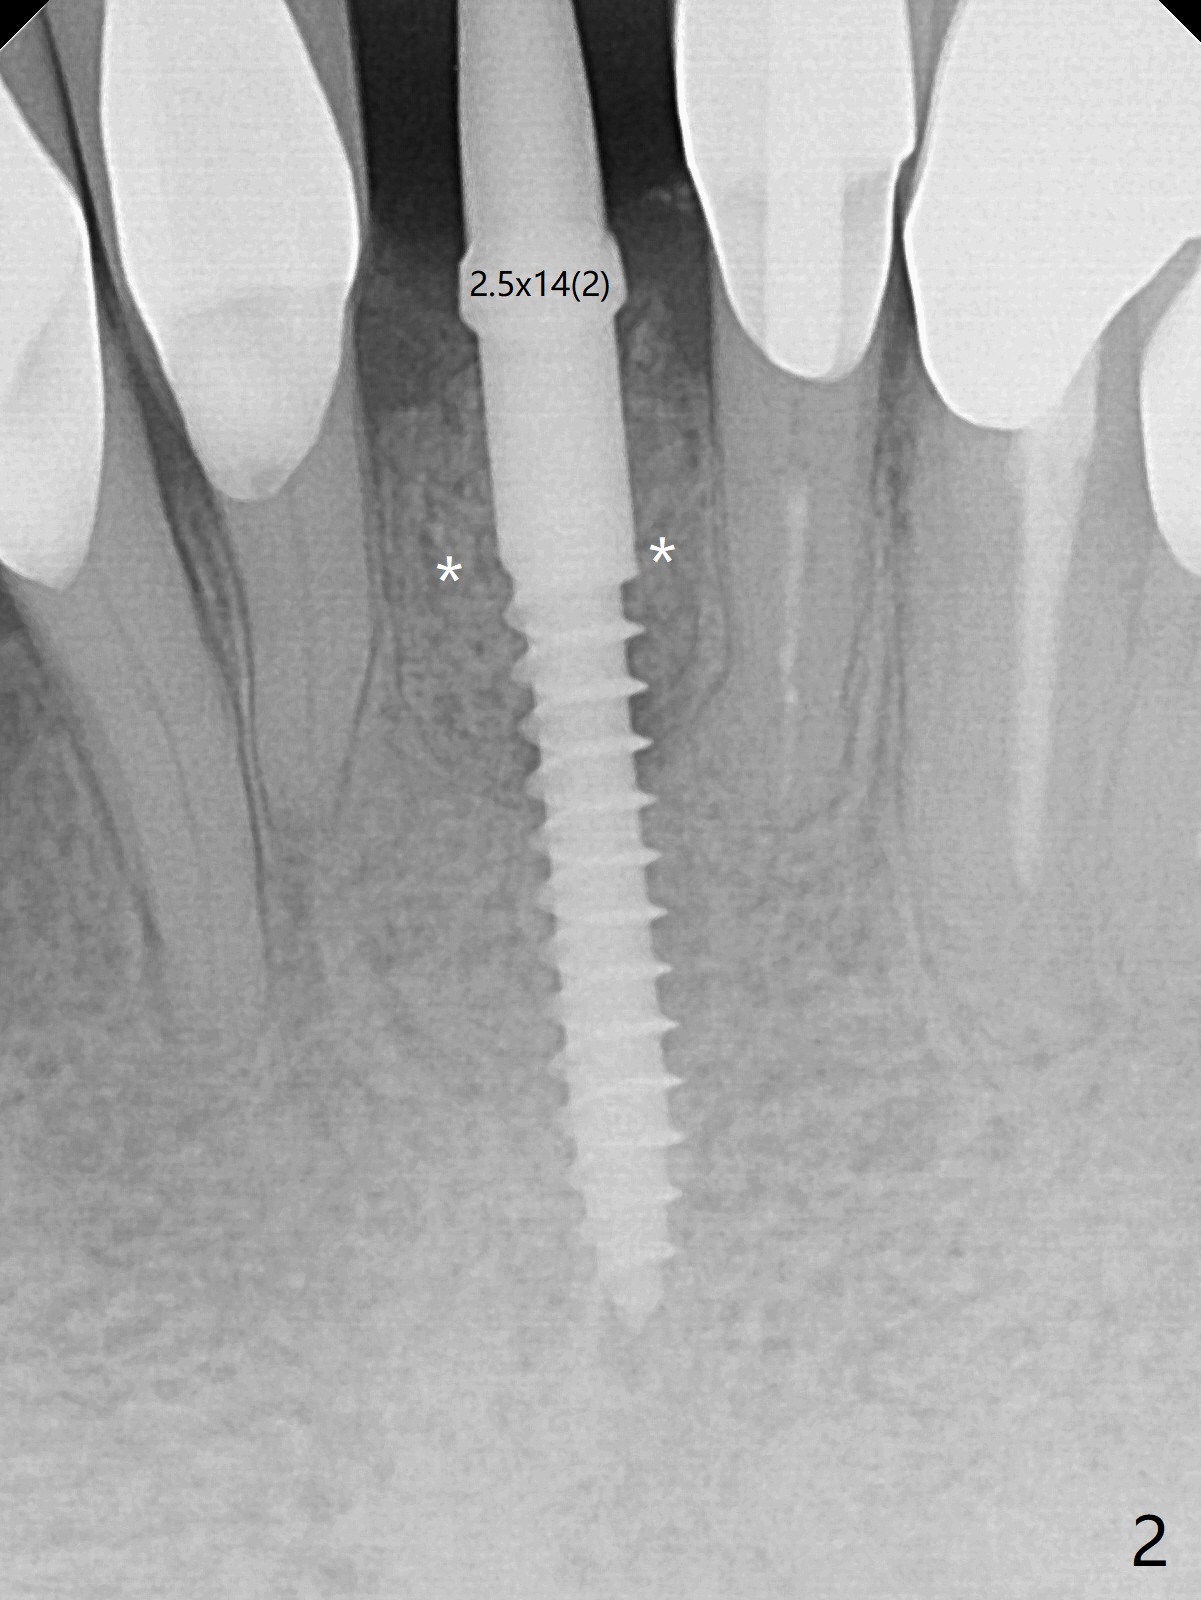

After extraction of the tooth #24 with vertical root fracture (loss of buccolingual plates), osteotomy is initiated with 1.2 mm drill free hand; the trajectory seems satisfactory (Fig.1). With sequential osteotomy, a 2.5x14(2) mm 1-piece implant has difficulty being placed deep (Fig.2), apparently associated with dense bone. Allograft is placed not only mesiodistal (Fig.2,4 *), but also buccolingual (Fig.3,5,6 *) to cover the exposed implant threads. In fact inability to place the implant deep is due to the apex of the implant (Fig.5,6 x) touching the lingual (L) cortical plate. If surgical guide were used, the implant placement difficulty would not occur. The surgery would be shorter and easier. The seemingly easiest implant placement should be assisted with a guide! In addition, preop CT would dictate implant placement in the middle of the socket buccolingual. The lingual (Fig.7 *) and buccal (Fig.8 <) gingiva remains bulky, although asymptomatic, 8 days postop.